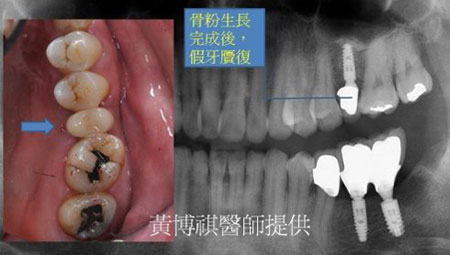

最後等人工骨粉癒合,作上假牙,回復正常咬合功能。 |